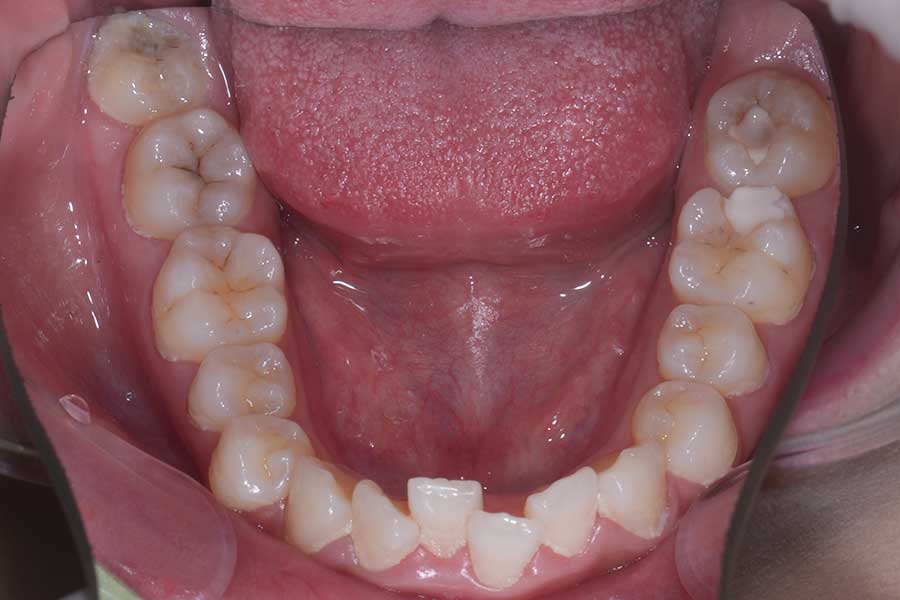

治療後

主訴 前歯の形と並びを良くしたい

治療内容 上下顎リンガル矯正(裏側矯正)